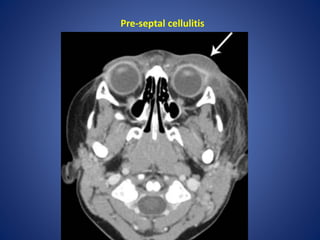

Orbital and periorbital cellulitis

It is important to differentiate between orbital and periorbial

cellulitis, as this has theraputic and prognostic implications:

1. peri-orbital cellulitis (pre-septal cellulitis) is limited to the soft

tissues anterior to the orbital septum. This condition is often

managed with oral antibiotics

2. orbital cellulitis refers to a post-septal infection (i.e. is behind or

extends posterior to the orbital septum). This is a more serious

condition requiring hospitalisation and parental antibiotics.

Complications such as intraorbital abscess formation may require

surgical intervention

Pre-septal cellulitis

• #39 Axial contrast-enhanced CT image of the orbit shows soft tissue thickening of the right preseptal region (between arrows). The retroorbital fat is normal (arrowheads).